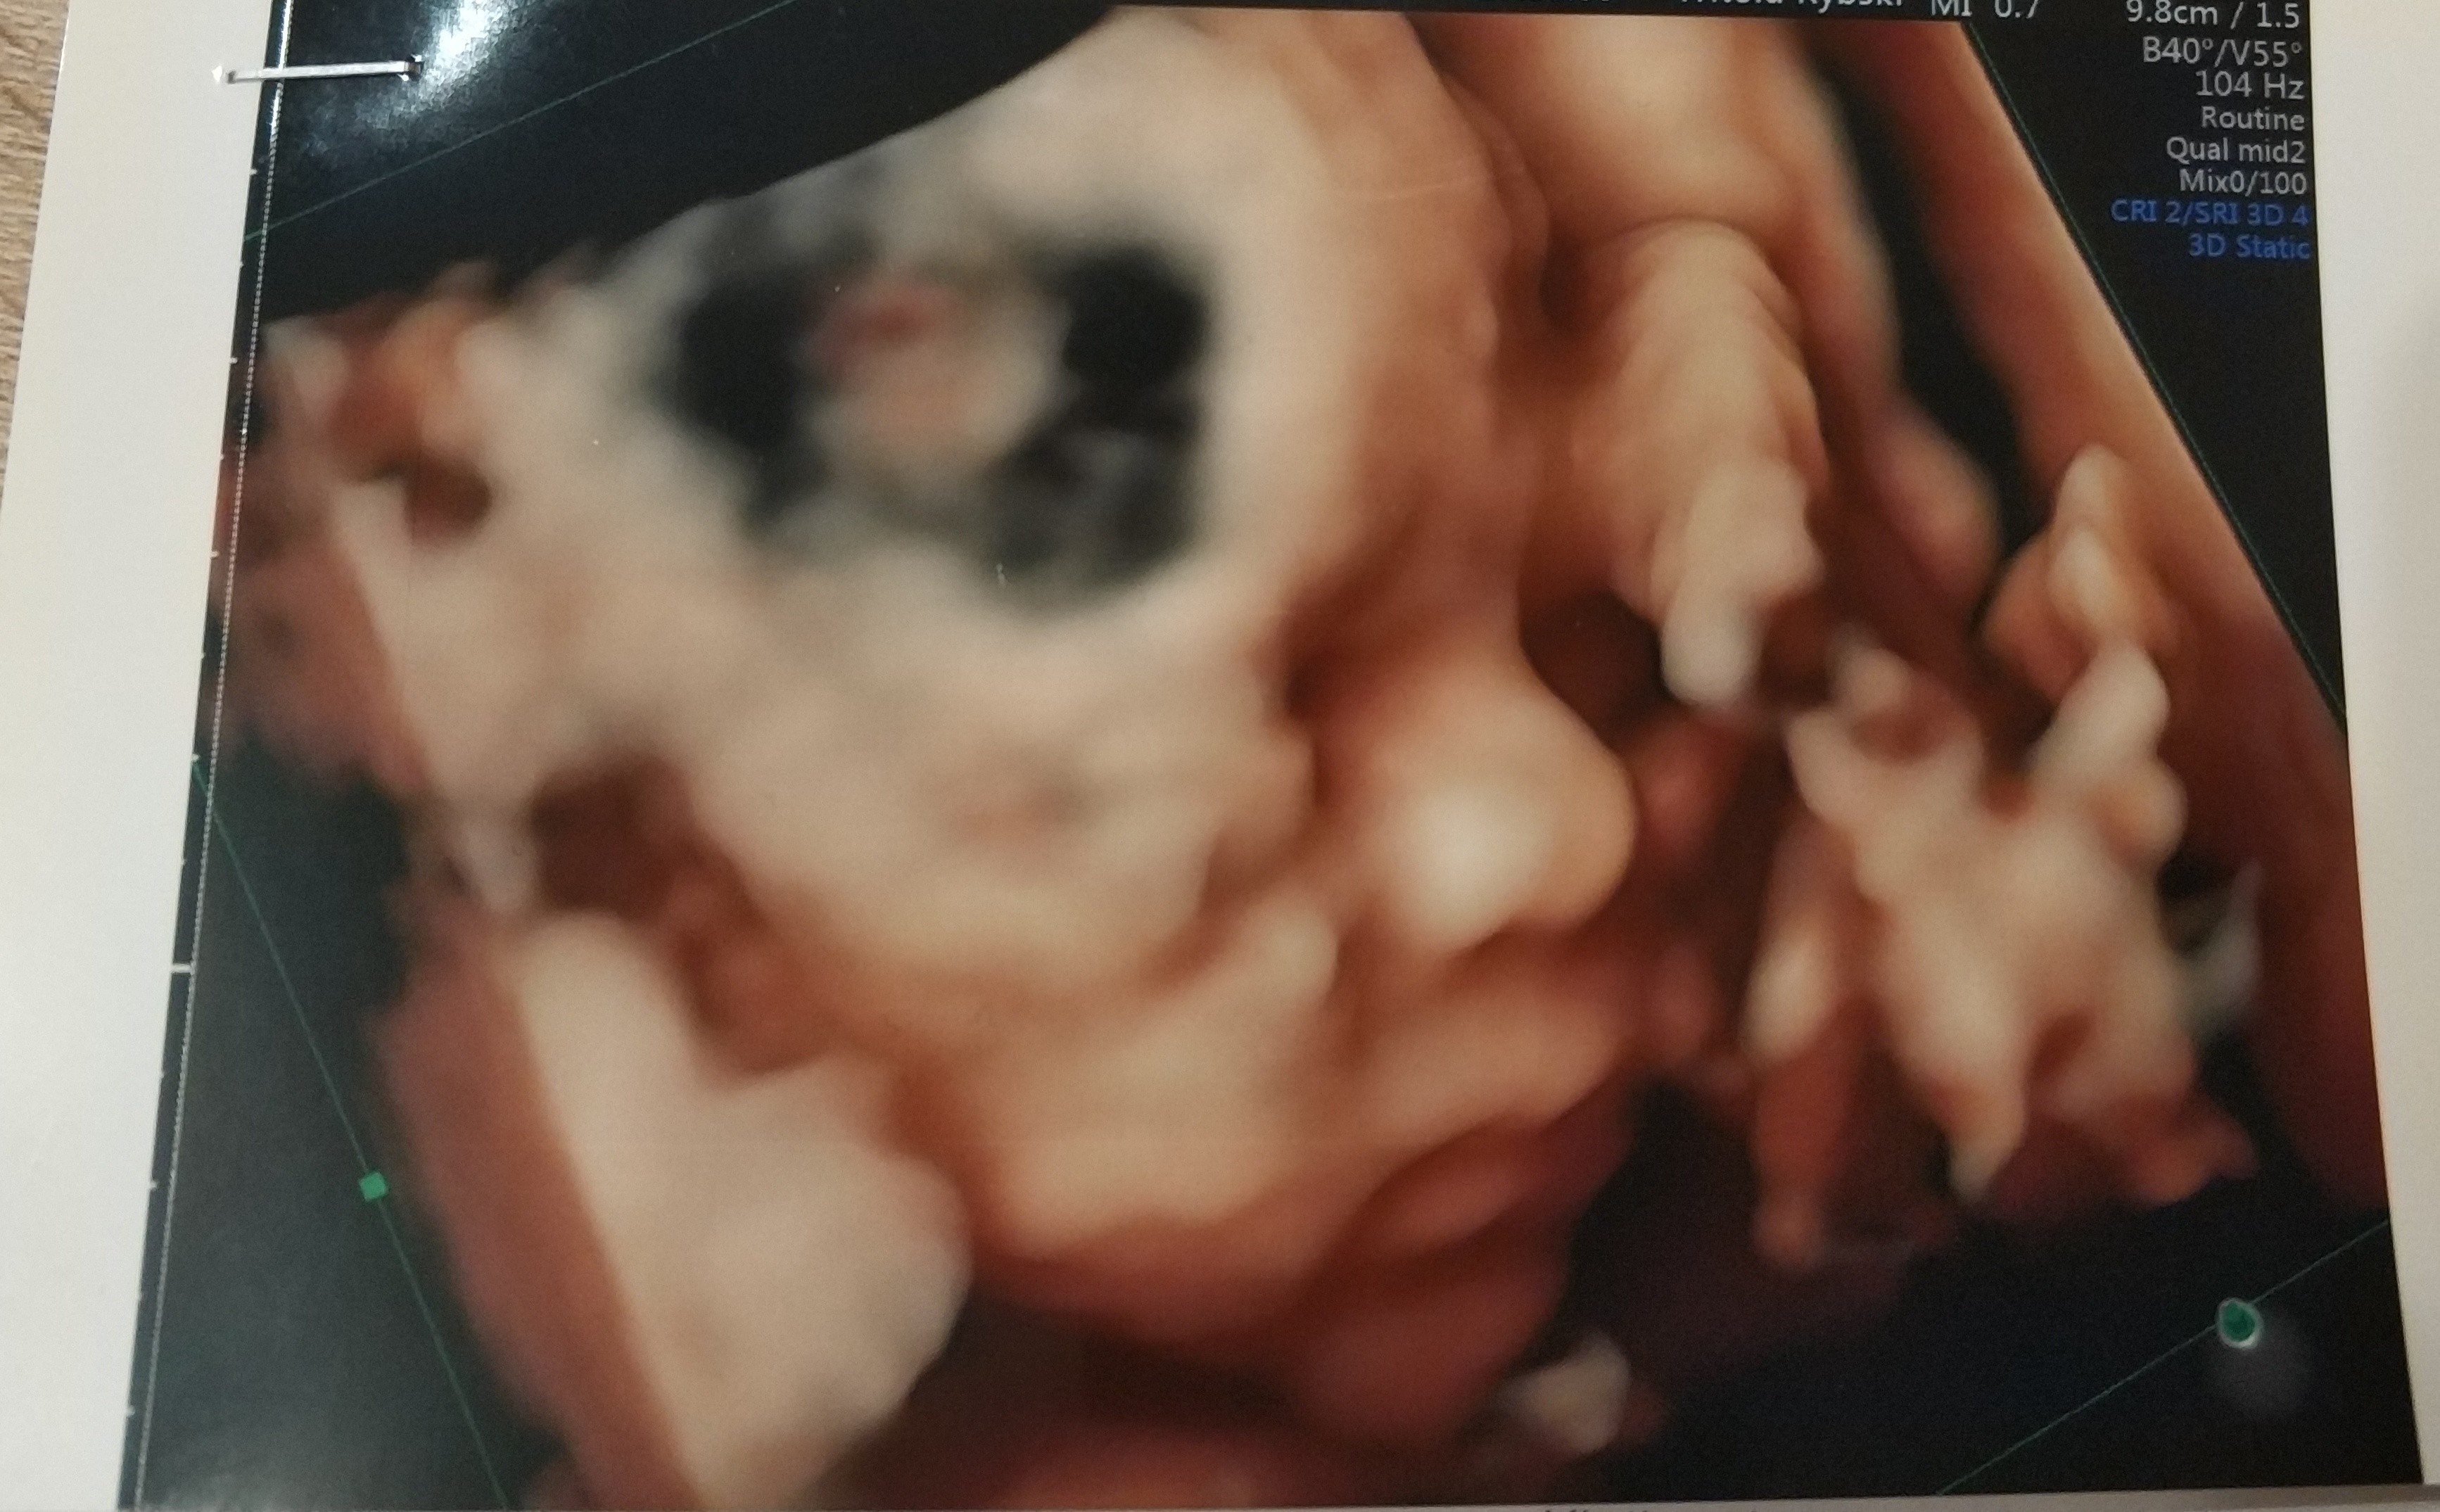

Hej. nie mialam kiedy napisac bo niedawno wrocilismy do domu.

Z synkiem wszystko jest super.

lekarz nie doszukal sie zadnej wady narzadów czy genetycznych.

Synus rosnie w siłę i odpowiada 25tc. Ogolnie kazal skontrolowac za 7-9 tyg. wage dziecka bo wyglada na to ze bedzie spory. do tego ulozony na poczatku posladkowo a finalnie poprzecznie. to sie moze z milion razy zmienic ale niezly kombinator z niego. Pan doktor zaznaczyl nam na usg siusiaczka nazywajac go armatką i ze na pewno bedzie straszyl kolezanki w przedszkolu :p

na zdj wyglada jak nasza corcia gdy sie urodzila :p wazy juz 700g :p